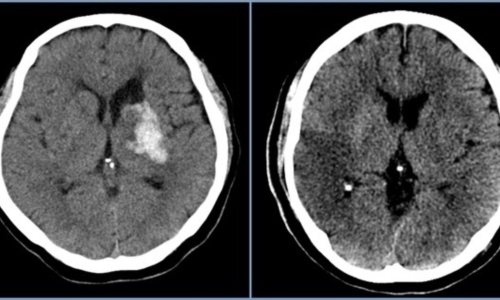

뇌졸중에서도 혈관이 막히는 뇌경색이야말로 촌각을 다투는 응급질환이라고 볼 수 있습니다. 뇌혈관이 막히면서 점차 뇌세포가 괴사하기 때문에, 증상 발현 3시간 안에 혈전용해제를 투여하고 시술에 들어가야 심각한 상황을 면할 수 있습니다. 뇌경색 치료방법에 있어 가장 중요한 것은 혈전을 녹이는 혈전용해제를 정맥 투여함으로써 막힌 혈관을 뚫어주는 것입니다. 하지만 혈전용해제의 경우도 출혈 가능성이 있는 환자에게는 투여할 수 없으며, 또한 혈소판 수치가 낮아서 지혈이 되지 않는 경우에는 제외된다고 합니다.

또한 과거에 이미 뇌출혈이 발생한 경우와 고혈압 환자의 경우도 혈전용해제를 투여할 수 없다으며 보통은 약50% 정도의 환자에게만 혈전 용해제를 이용한 치료가 가능합니다. 막힌 혈관을 뚫어주는 치료를 한 이후에도 뇌경색은 꾸준히 관리해야 하는데 재발할 확률이 높기 때문입니다. 따라서 약물치료와 함께 재활 치료가 필요하며 치료 이후 초기에 재활 치료를 적극적으로 해야 뇌경색 치료방법의 효과가 크고 후유증을 줄일 수 있습니다.